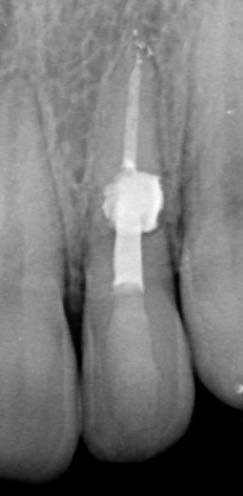

The patient started orthodontic treatment, however, tooth 2.2 was temporarily not included in the orthodontic therapy at the endodontist's request, who was willing to observe it for a year. Furthermore, increased resorption could have been provoked. As of today, the tooth is included in the orthodontic treatment and is being followed up.

In eighteen-month time, the stabilized process is observed, meaning that the diagnosis has been correct and the manual work has been performed without problems. No complaints are observed.

The difference between internal and external resorption lies in the fact that high-quality removal of granulation tissue by mechanical and chemical (calcium hydroxide) techniques allows for achieving a high level of recuperation. Also, an accurate DI diagnosis makes it possible to seal the invaginated area at the early stages before pulp-associated complications occur, which would later require comprehensive endodontic treatment. Other approaches and tactics for treating teeth with invaginations are described in previous articles by the authors.